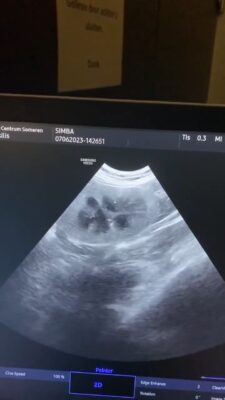

Its about a dog, 1,5 years old, intact, Tervuerense Herder X Groenedaeler which has since one month ago according with the owner, gagging symptoms. The owner mentioned that sometimes the dog coughs and then he vomit some white <<foam>> . The dog eats barf…

The radiologist mentioned also that there is a suspicion of an old trauma but because the <<instellings>> of the xrays might not be the best, it might be also an artifact.